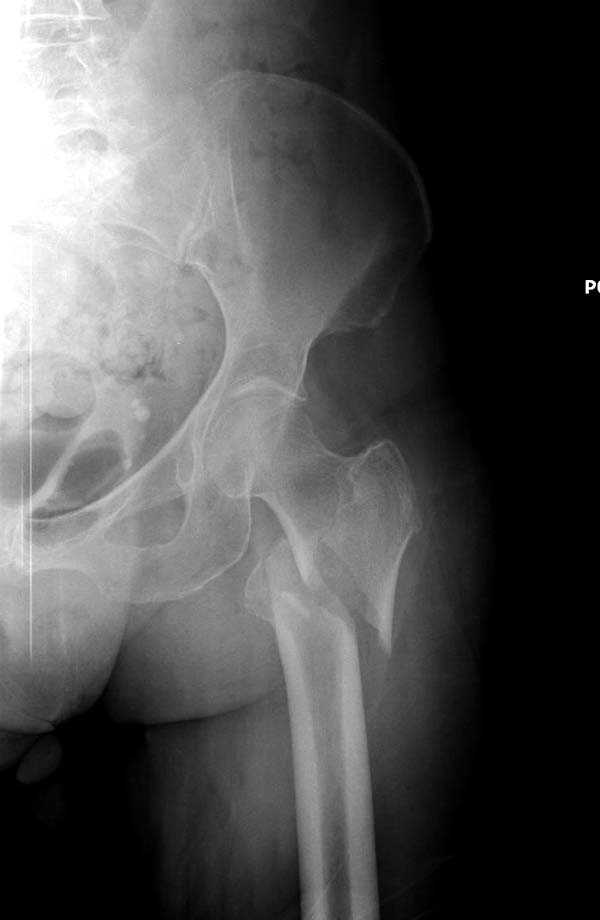

Для лечения переломов проксимального бедра существует различные конструкции, включая цефаломедуллярные. Среди них из-за простоты и удобной конструкции распространенным является Gamma.

Здесь представлен случай, где в послеоперационном периоде обнаружена техническая ошибка, Gamma 3 установлен с нарушением методики. Больная в 91 лет, прооперирована через день после поступления и выписана через 48 часов.<br>

При первом послеоперационном поликлиническом осмотре больная предъявила жалобы на боли в бедре. В серийных снимках обнаружен продольный перелом верхнего отдела бедра.<br>